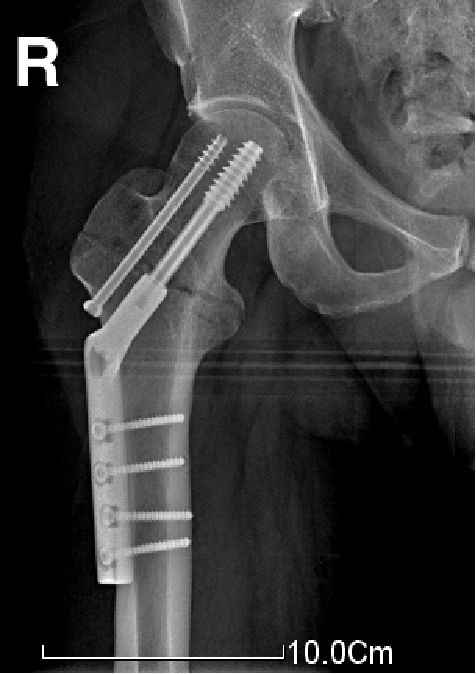

PFNA(股骨近端螺旋刀片抗旋髓内钉proximal femoral nail anti-rotation blade)

新改进的PFN(股骨近端髓内钉)系统,一方面继承了原PFN 的优点,生物力学特点相同,另一方面在具体设计上有所创新,令固定更有效、操作更简单。

刀片具有宽大的表面积和逐渐增加的芯直径(4.5-9mm),通过打入,填压松质骨,可提高其锚合力,尤其适合骨质疏松患者。

与骨质贴合紧密,增强了稳定性,抗旋转、抗骨折端塌陷和内翻畸形的能力很强。

适用于几乎所有的转子间骨折,特别适合于不稳定型骨折(如反转子间骨折)及合并骨质疏松者。

反转子间骨折

仍有一定的并发症发生率(如穿出股骨头),因此无法取代其他内固定。